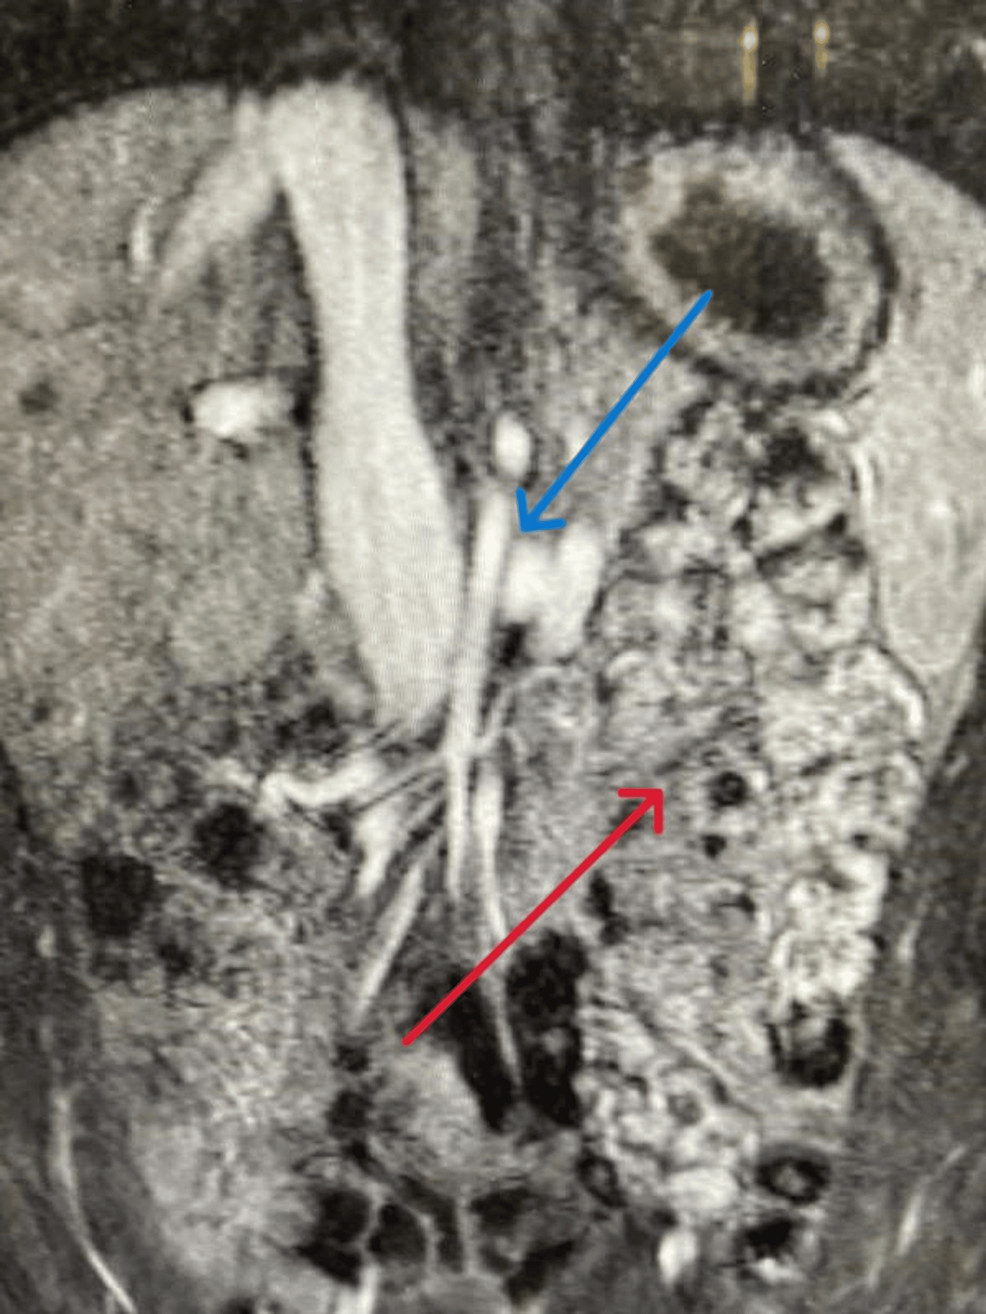

From radiopaedia.org